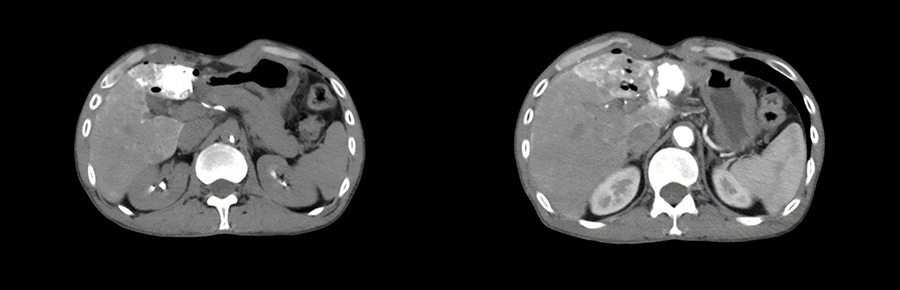

患者二

44岁男性,因“诊断HCC2年余,腹痛1周。”入院,完善上腹部MRI及肿瘤指标,考虑肿瘤复发.影像检查显示:肝S3段异常信号范围较前略增大。综合平扫+DWI诊断:肝S3、4、8段异常信号,考虑Ca介入术后改变,未见明显活性残留,肝S3段考虑Ca复发,范围较前略增大。肝尾叶略大,肝实质多发增生结节。病灶大小约为3.5(左右)x3cm(胸背)x3cm(头足)。

▲ 患者二术前影像